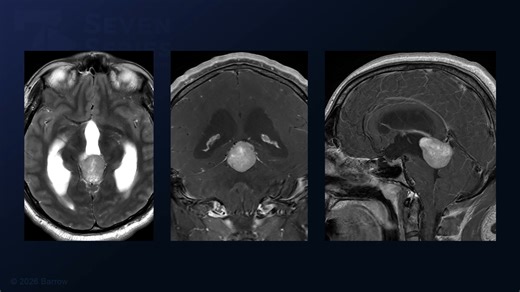

Infratentorial Stroke - MRI Scan of

the Brain - Mastoid

Anatomy - Tentorial

Meningioma - Brain

Stem